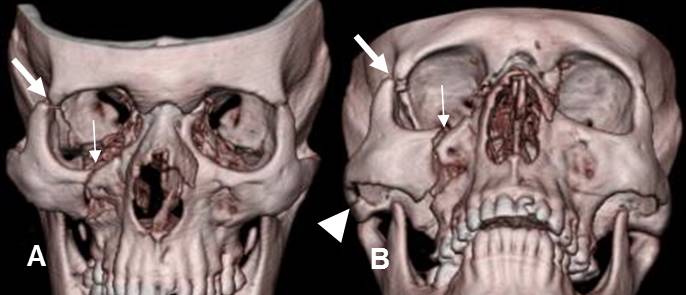

Fig 212. Fractura trimalar.

A y B: TAC axial. Fracturas en el piso y pared posterior del antro maxilar derecho.

Hay fractura cabalgada del arco cigomático del mismo lado.

Fig 213. Fractura trimalar.

A y B: TAC reconstrucción 3D. Fractura trimalar con lesión de la unión cigomático-maxilar (Flecha delgada), cigomático-frontal (Flecha gruesa) y cigomática-temporal (Punta de flecha).